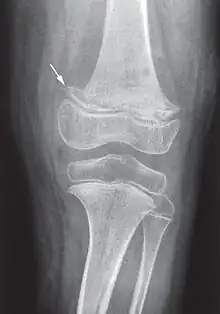

Radiographie d'un genou scorbutique. La flèche indique le départ d'une « ligne scorbutique » : bande très dense séparée de la diaphyse par une étroite zone claire non homogène.

Il s'agit d'un scorbut infantile (nourrisson ou petit enfant) décrit par le médecin anglais Thomas Barlow (1er baronnet) (1845-1945) qui distingue cette maladie du rachitisme en 1883. Ce scorbut survient dans les couches sociales aisées. La maladie est due à l'abandon de l'allaitement maternel pour les premiers laits industriels (lait de vache bouilli) dépourvus de vitamine C (détruite par les processus de chauffage). La « maladie de Barlow » sera éliminée par l'ajout de jus d'orange dans le biberon[5].

Elle débute par une perte d'appétit, un arrêt de la prise de poids, une pâleur, suivis d'un syndrome douloureux des membres entraînant agitation, cris et insomnie (pleurs à la mobilisation des membres). Les signes osseux sont au premier plan : à la palpation douce, on trouve des tuméfactions osseuses, surtout au niveau du fémur ou des articulations chondrosternales (entre le sternum et les côtes, parfois appelées le « rosaire scorbutique »). La gingivite n’apparaît qu'avec les premières poussées dentaires[19].

Les douleurs osseuses sont liées aux hémorragies sous-périostées. La radiographie peut montrer les troubles du périoste (hématomes sous-périostés) et de la structure osseuse (ostéoporose avec aspect en « verre pilé », la « ligne scorbutique » séparant la diaphyse des extrémités, élargissement de l'extrémité antérieure des côtes...)[19].